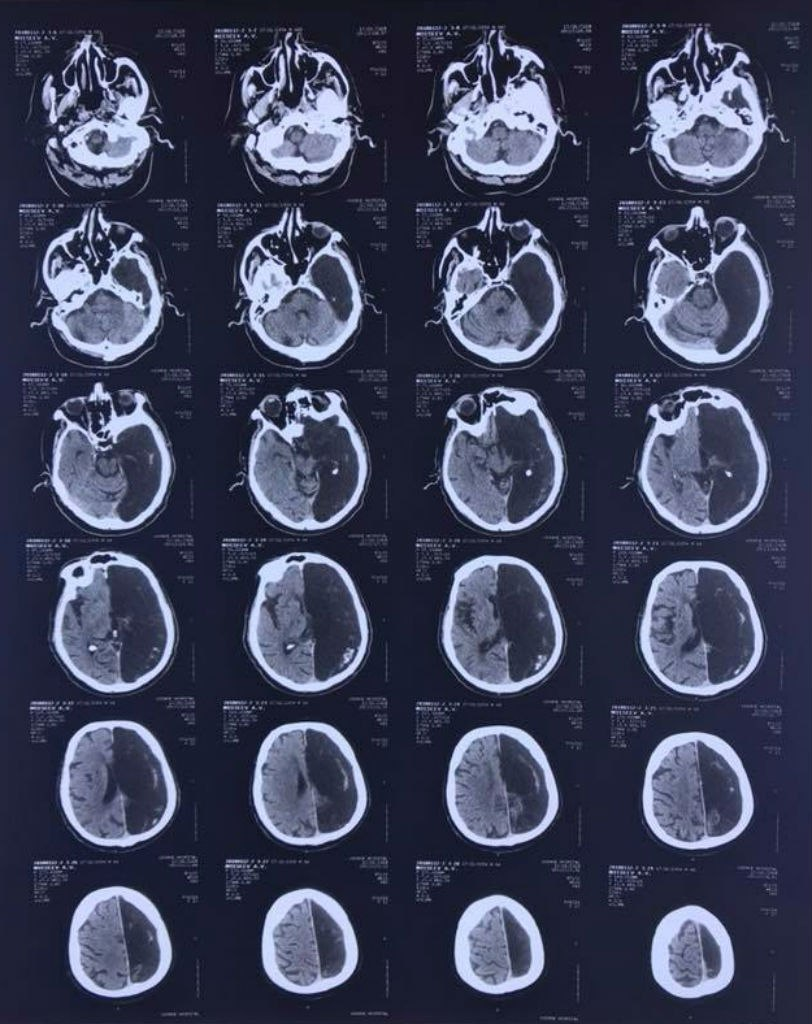

Коли радіологи зробили йому КТ, деякий час перебували у подиві — у пенсіонера була відсутня та частину мозку, де сталася та сама ішемічна атака.

Замість лівої півкулі на знімку зяяла "чорна дірка". Неврологи зробили висновок, що функції всього мозку у цієї людини все життя виконувала тільки права півкуля.